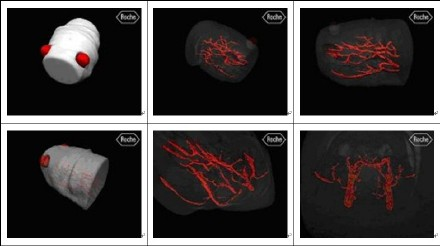

(12)IDL在药物研究中的应用

位于瑞士巴塞尔的核磁共振实验室应用IDL进行药物研究。应用核磁共振影像,不需要活体注入等工作即可完成对常规生理参数的测量。

Fig 12:IDL可视化技术在医学制药研究中的应用